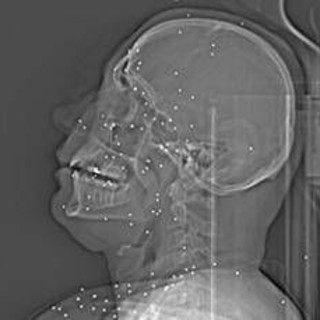

L'inchiesta horror sulle violenze iraniane: 'Manifestanti uccisi e colpiti nelle parti vitali'